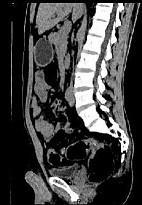

问题 女,51岁,腹胀、腹痛、进行性消瘦,影像检查如下图,最佳诊断是()

选项 A.乙状结肠Crohn病 B.乙状结肠结核 C.乙状结肠癌 D.乙状结肠淋巴瘤 E.乙状结肠息肉

答案 C